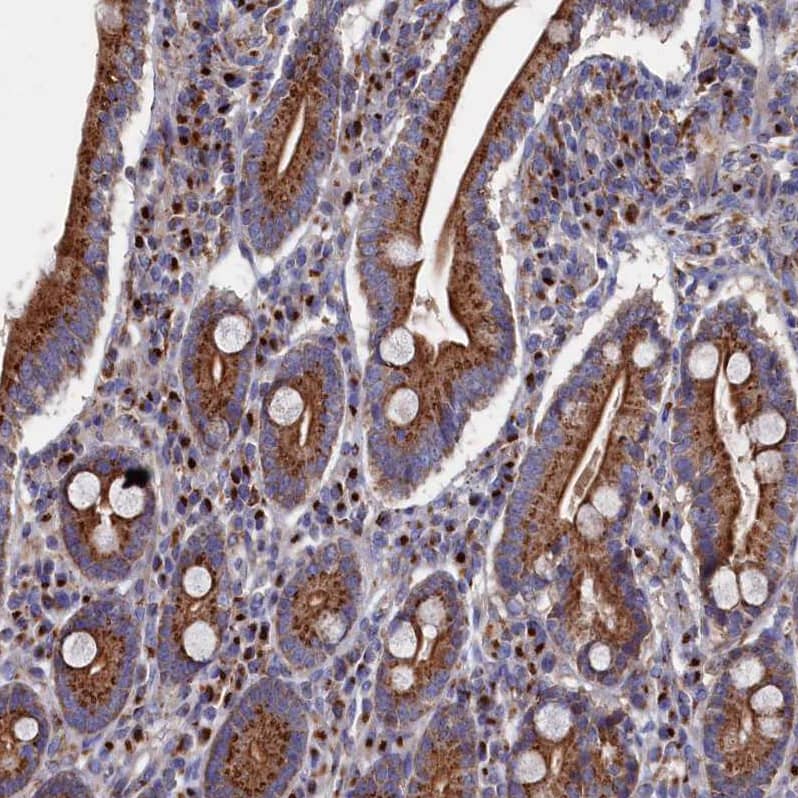

Staining of human duodenum shows strong cytoplasmic granular positivity in glandular cells.